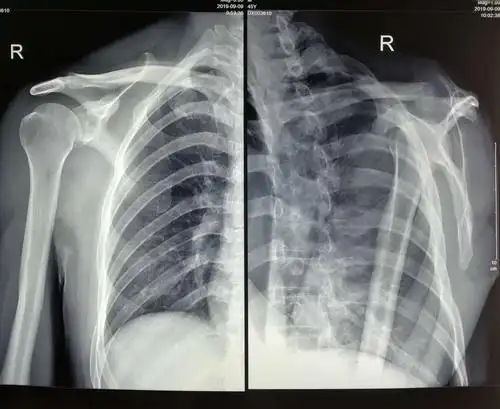

右肩冻结肩关节镜下松解诊治术